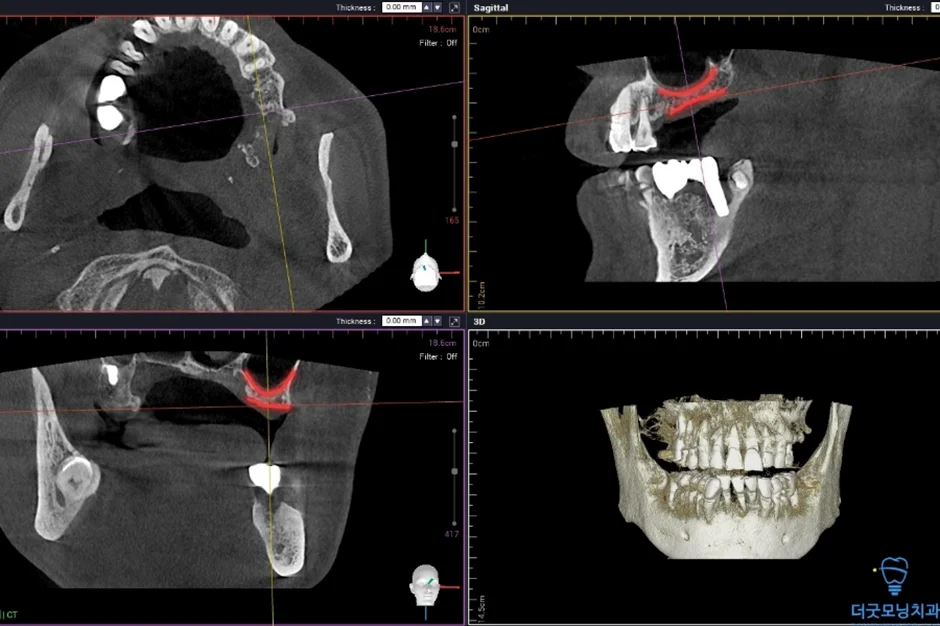

2. 검진 결과 — 파노라마 엑스레이 & CT 분석

먼저 파노라마 엑스레이와 CT를 통해 구강 전체 상태를 확인하였습니다.

상악동이 많이 함기화되어 있어 상악동 골이식(치조정 접근 상악동 거상술)이 반드시 필요한 상태였습니다. CT 확인 결과 가용골이 매우 부족한 것이 명확히 확인되었습니다.

Q. 상악동 골이식(상악동 거상술)은 어떤 수술인가요?

A. 위 어금니 부위에 임플란트를 심을 때 뼈의 양이 부족한 경우, 상악동(코 옆 공간)의 바닥을 들어올려 뼈를 보충하는 수술입니다. 치조정 접근법은 임플란트 식립과 동시에 진행할 수 있어 치료 횟수를 줄일 수 있는 방식입니다.